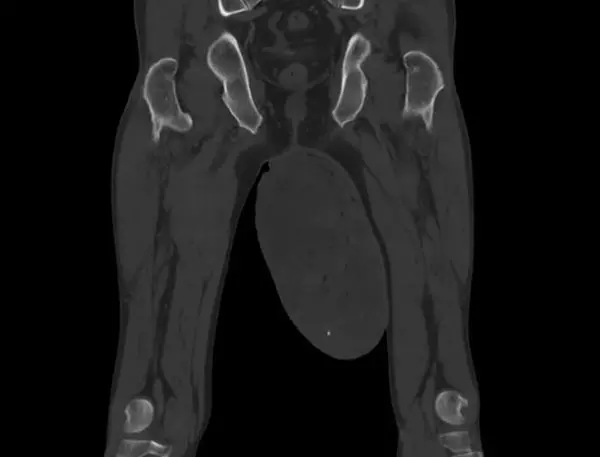

CT(컴퓨터단층촬영)과 MRI(자기공명영상) 검사 결과, 왼쪽 음낭 안에서 가로 25cm, 세로 15cm 크기의 거대한 덩어리가 발견됐다. 의료진은 곧바로 왼쪽 음낭을 25cm가량 절개해 덩어리를 제거하는 수술을 시행했다. 다행히 음낭 안에 있는 고환과 부고환에는 이상이 없는 것으로 확인됐다. 조직검사 결과, 이 덩어리는 혈관근섬유모세포종으로 진단됐다.

혈관근섬유모세포종은 대부분 통증 없는 작은 덩어리로 시작한다. 시간이 지나 크기가 커지면 음낭이 부어오르거나 불편감을 유발할 수 있으며, 종양 내부에 혈관이 많아 출혈이나 부종이 생기기도 한다. 혈관근섬유모세포종은 먼저 초음파 검사로 종양의 위치와 경계를 파악한다. 이후 주변 조직 침범 여부 확인하기 위해 MRI와 CT 검사를 진행한다. 마지막으로 수술적 절제 후 조직검사를 통해 확정 진단을 내린다.